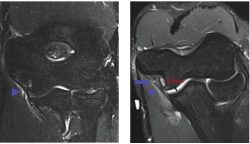

20-year-old male pitcher with acute medial elbow pain after pitching.

A, Coronal standard (A) and flexed elbow valgus external rotation (FEVER) (B) MR images show low-grade partial ulnar collateral ligament tear (arrow, B), which is more evident on FEVER image. Periligamentous edema (arrowhead) is evident in both views. FEVER view shows mild ulnotrochlear joint space widening to 4.3 mm (black line, B).